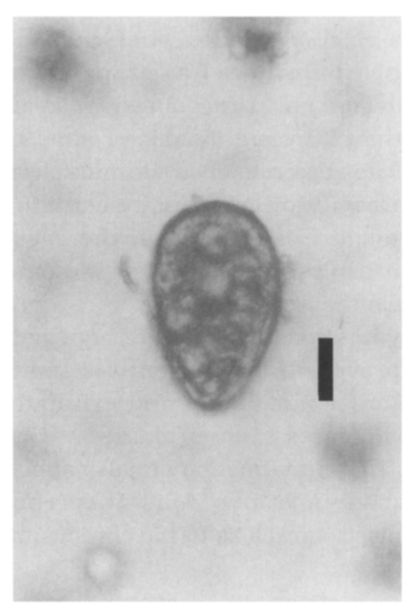

The masses surrounding the lesions in the temporo-occipital lobe were resected on May 20, 1997 and then in the frontal lobe on June 8, 1997 through the craniotomies. The resected masses were yellowish and looked like a branch of grape. Paragonimus westermani eggs were identified under light microscope from the stamp smears of the resected tissues (Fig. 2). The eggs were 81.6 ± 2.9 µm in length and 52.8 ± 2.0 µm in width. This case was diagnosed to be a cerebral paragonimiasis by P. westermani eggs. Pathologic preparations revealed the P. westermani eggs were concentrated near a border of the fibrous worm capsule and scattered in the calcified nodular lesions (Fig. 3). Any remnant of P. westermani was not found in the necrotic worm capsule, except for the eggs.

Radiologic findings for cerebral paragonimiasis have been recorded to be conglomerates of multiple ring-shaped shadows or enhancements so-called "grape cluster" or "soap bubble" formed in one hemisphere in general (Cha et al., 1994; Kadota et al., 1989), and the present case showed a "grape cluster". In chronic cerebral paragonimisis, persisting for more than 20 years (Katoda et al., 1989), the worm capsules remained as multiple nodules with a cavity of low density containing the Paragonimus eggs. Most of the eggs in the worm capsules retained a shell without yolk as shown in the present case.